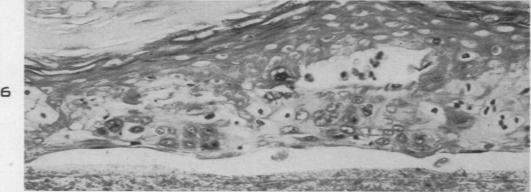

The Pathology of High-Altitude Frostbite.

Am J Pathol. 1947 Mar;23(2):173-87.

Experimental frost-bite in Hanford Miniature Swine. I. Epithelial changes.汉福德小型猪的实验性冻伤。I. 上皮变化。

Br J Exp Pathol. 1989 Feb;70(1):41-9.